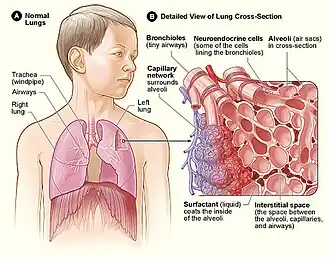

Humans have two lungs, a right lung and a left lung. They are situated within the thoracic cavity of the chest. The right lung is bigger than the left, and the left lung shares space in the chest with the heart. The lungs together weigh approximately 1.3 kilograms (2.9 lb), and the right is heavier. The lungs are part of the lower respiratory tract that begins at the trachea and branches into the bronchi and bronchioles, which receive air breathed in via the conducting zone. These divide until air reaches microscopic alveoli, where gas exchange takes place. Together, the lungs contain approximately 2,400 kilometers (1,500 mi) of airways and 300 to 500 million alveoli. Each lung is enclosed within a pleural sac of two pleurae which allows the inner and outer walls to slide over each other whilst breathing takes place, without much friction. The inner visceral pleura divides each lung as fissures into sections called lobes. The right lung has three lobes and the left has two. The lobes are further divided into bronchopulmonary segments and lobules. The lungs have a unique blood supply, receiving deoxygenated blood sent from the heart to receive oxygen (the pulmonary circulation) and a separate supply of oxygenated blood (the bronchial circulation).

Microanatomy

The lungs are part of the lower respiratory tract, and accommodate the bronchial airways when they branch from the trachea. The bronchial airways terminate in alveoli which make up the functional tissue (parenchyma) of the lung, and veins, arteries, nerves, and lymphatic vessels.[3][15] The trachea and bronchi have plexuses of lymph capillaries in their mucosa and submucosa. The smaller bronchi have a single layer of lymph capillaries, and they are absent in the alveoli.[16] The lungs are supplied with the largest lymphatic drainage system of any other organ in the body.[17] Each lung is surrounded by a serous membrane of visceral pleura, which has an underlying layer of loose connective tissue attached to the substance of the lung.[18]

All of the lower respiratory tract including the trachea, bronchi, and bronchioles is lined with respiratory epithelium. This is a ciliated epithelium interspersed with goblet cells which produce mucin the main component of mucus, ciliated cells, basal cells, and in the terminal bronchioles–club cells with actions similar to basal cells, and macrophages. The epithelial cells, and the submucosal glands throughout the respiratory tract secrete airway surface liquid (ASL), the composition of which is tightly regulated and determines how well mucociliary clearance works.[21]

Pulmonary neuroendocrine cells are found throughout the respiratory epithelium including the alveolar epithelium,[22] though they only account for around 0.5 percent of the total epithelial population.[23] PNECs are innervated airway epithelial cells that are particularly focused at airway junction points.[23] These cells can produce serotonin, dopamine, and norepinephrine, as well as polypeptide products. Cytoplasmic processes from the pulmonary neuroendocrine cells extend into the airway lumen where they may sense the composition of inspired gas.[24]

Respiratory zone

The conducting zone of the respiratory tract ends at the terminal bronchioles when they branch into the respiratory bronchioles. This marks the beginning of the terminal respiratory unit called the acinus which includes the respiratory bronchioles, the alveolar ducts, alveolar sacs, and alveoli.[27] An acinus measures up to 10 mm in diameter.[28] A primary pulmonary lobule is the part of the lung distal to the respiratory bronchiole.[29] Thus, it includes the alveolar ducts, sacs, and alveoli but not the respiratory bronchioles.[30]

The unit described as the secondary pulmonary lobule is the lobule most referred to as the pulmonary lobule or respiratory lobule.[25]: 489 [31] This lobule is a discrete unit that is the smallest component of the lung that can be seen without aid.[29] The secondary pulmonary lobule is likely to be made up of between 30 and 50 primary lobules.[30] The lobule is supplied by a terminal bronchiole that branches into respiratory bronchioles. The respiratory bronchioles supply the alveoli in each acinus and is accompanied by a pulmonary artery branch. Each lobule is enclosed by an interlobular septum. Each acinus is incompletely separated by an intralobular septum.[28]

The respiratory bronchiole gives rise to the alveolar ducts that lead to the alveolar sacs, which contain two or more alveoli.[20] The walls of the alveoli are extremely thin allowing a fast rate of diffusion. The alveoli have interconnecting small air passages in their walls known as the pores of Kohn.[20]

Alveoli

Alveoli consist of two types of alveolar cell and an alveolar macrophage. The two types of cell are known as type I and type II cells[32] (also known as pneumocytes).[3] Types I and II make up the walls and alveolar septa. Type I cells provide 95% of the surface area of each alveoli and are flat ("squamous"), and Type II cells generally cluster in the corners of the alveoli and have a cuboidal shape.[33] Despite this, cells occur in a roughly equal ratio of 1:1 or 6:4.[32][33]

Type I are squamous epithelial cells that make up the alveolar wall structure. They have extremely thin walls that enable an easy gas exchange.[32] These type I cells also make up the alveolar septa which separate each alveolus. The septa consist of an epithelial lining and associated basement membranes.[33] Type I cells are not able to divide, and consequently rely on differentiation from Type II cells.[33]

Type II are larger and they line the alveoli and produce and secrete epithelial lining fluid, and lung surfactant.[34][32] Type II cells are able to divide and differentiate to Type I cells.[33]

The alveolar macrophages have an important role in the immune system. They remove substances which deposit in the alveoli including loose red blood cells that have been forced out from blood vessels.[33]

Respiratory tract

The lower respiratory tract is part of the respiratory system, and consists of the trachea and the structures below this including the lungs.[32] The trachea receives air from the pharynx and travels down to a place where it splits (the carina) into a right and left primary bronchus. These supply air to the right and left lungs, splitting progressively into the secondary and tertiary bronchi for the lobes of the lungs, and into smaller and smaller bronchioles until they become the respiratory bronchioles. These in turn supply air through alveolar ducts into the alveoli, where the exchange of gases take place.[32] Oxygen breathed in, diffuses through the walls of the alveoli into the enveloping capillaries and into the circulation,[20] and carbon dioxide diffuses from the blood into the lungs to be breathed out.